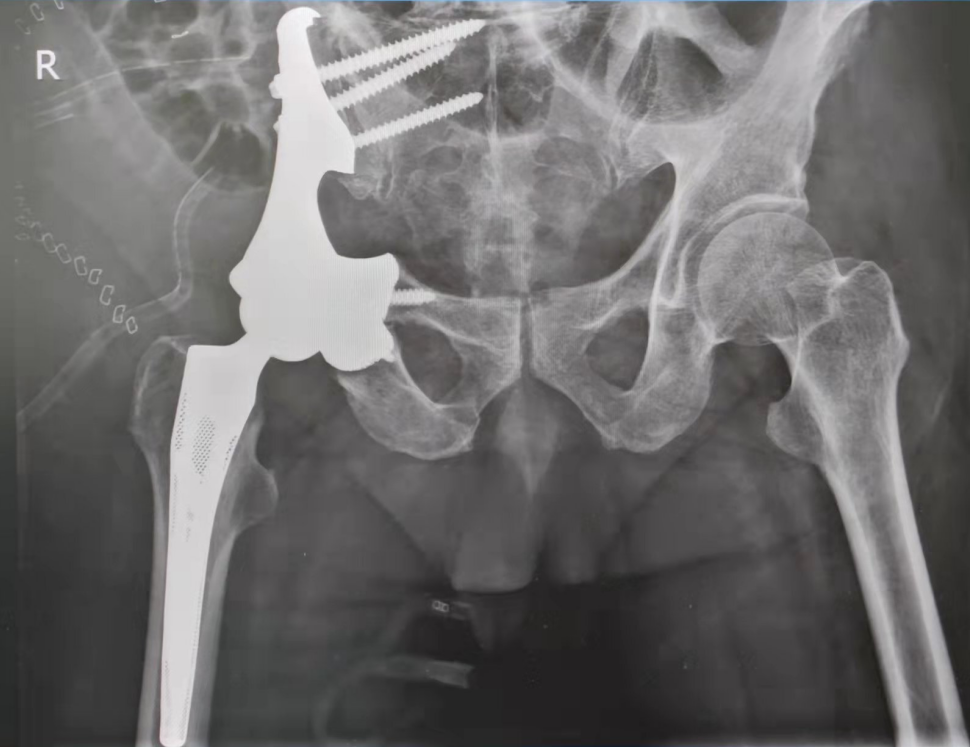

产品特性: 优异生物相容性;仿生骨小梁的多孔设计,促进骨长入与血管化,实现生物固定;精准匹配定制,契合复杂骨盆缺损解剖结构;力学性能突出: 高强度、低弹性模量(接近人骨)、耐磨耐腐蚀,满足承重需求。

应用适应症:主要用于因骨盆恶性肿瘤切除、严重创伤或感染导致的半骨盆大面积骨质缺损的解剖结构和功能重建。